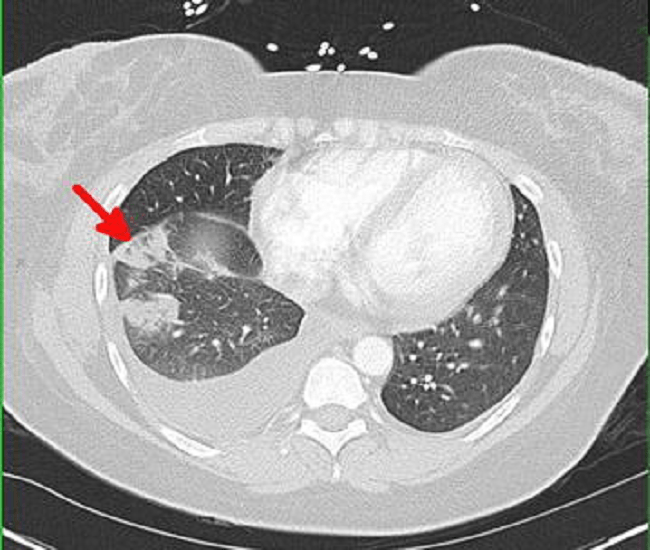

Infark paru terjadi ketika terdapat sumbatan dari arteri pulmoner distal. Hal ini dapat menyebabkan iskemia dan nekrosis jaringan di sekitarnya hingga terjadi perdarahan. Infark paru umumnya terjadi karena penyakit primer lainnya seperti emboli paru.

Sirkulasi ganda pada paru–paru, yaitu sirkulasi pulmonal yang berfungsi dalam proses pertukaran gas, dan sirkulasi bronkial yang berfungsi mensuplai darah ke dinding bronkial, pleura dan parenkim paru. Sirkulasi ganda pada paru–paru ini membantu mencegah terjadinya iskemia pada paru. Walaupun demikian, obstruksi arteri pulmoner karena emboli paru akut tetap dapat menyebabkan infark paru.[1–4]